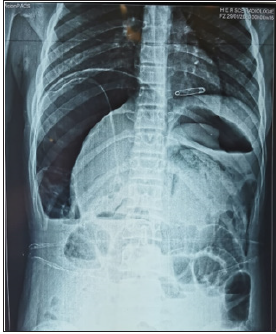

of acute generalized peritonitis was retained. X-ray examinations were performed to

support the etiological diagnosis. An abdominal X-ray was performed showing an enormous

pneumoperitoneum with probable mass pushing back the transverse colon and the digestive

loops at the bottom (Figure 1). An abdominal ultrasound showed a peritoneal effusion of great

Figure 1:Thoracoabdominal X-ray showing a huge pneumoperitoneum with backflow of the intestines at the bottom.